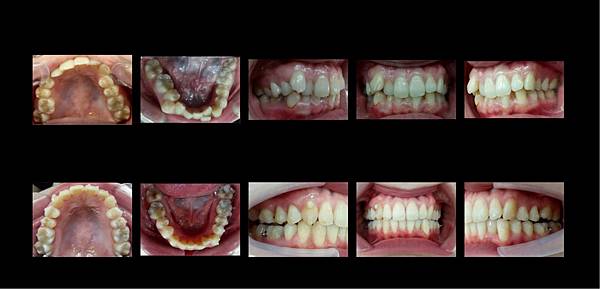

現在讓大家看看她做了一年隱適美的變化

順道一提,她是一個極度認真配戴的人,因為隱適美屬於自主性的矯正,它可以自由拿上拿下,所以大家一定要認真的配戴才會有好的結果喲